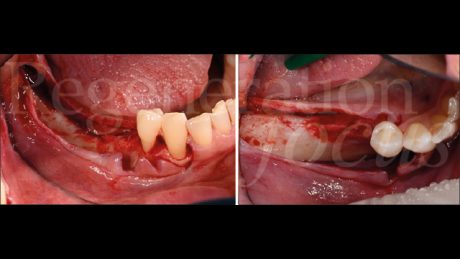

L’intervento chirurgico è stato eseguito in anestesia loco-regionale. È stato elevato un lembo trapezoidale composto da un’incisione crestale e da un’incisione verticale di svincolo posizionata due elementi mesialmente al difetto, mentre distalmente l’incisione è proseguita nella regione retromolare (Fig. 4). Particolare attenzione è stata posta al rilascio periostale, eseguito sia vestibolarmente che lingualmente, permettendo una mobilizzazione coronale di entrambi i lembi di circa 8 mm senza tensione.

La mesh customizzata si è adattata perfettamente al sito ricevente, confermando la precisione della pianificazione digitale (Fig. 5). Il materiale da innesto è stato preparato combinando osso autologo particolato, raccolto dalla linea obliqua esterna mediante grattino monouso (SafeScraper, Meta), con osso bovino deproteinizzato di granulometria 0,25-1 mm (Geistlich Bio-Oss®) in rapporto 50:50. A questa miscela sono stati aggiunti 0.3 ml di gel a base di polinucleotidi e acido ialuronico (Regenfast®), creando una mixture bioregenerativa che è stata accuratamente compattata all’interno della mesh (Fig. 6).

La fissazione è stata ottenuta mediante tre viti in titanio da 1.5×5 mm (Viti FYxoss, MCbio) posizionate strategicamente (Fig. 7). Una membrana in collagene 30×40 mm (Geistlich Bio-Gide®) è stata posizionata a copertura della mesh (Fig. 8). La chiusura primaria tension-free è stata ottenuta con suture orizzontali a materassaio e punti staccati (Fig. 9).